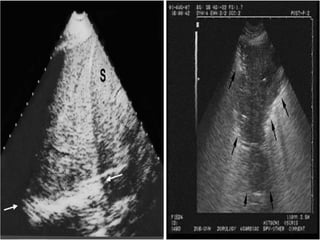

Tissue pattern representative of Alveolar

Consolidation

Presence of hyperechoic punctiform

imagesrepresentative of air bronchograms

Pleural

effusion

Lower lobe

Tissue pattern representativeof Alveolar Consolidation Presence of hyperechoic punctiform imagesrepresentative of air bronchograms Pleural effusion Lower lobe